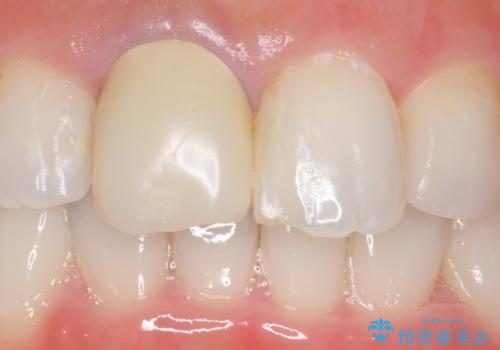

- 右上1の前歯の見た目が気になるので被せ物をやり替えたいといらっしゃった方の症例です。

再根管治療終了後、オールセラミッククラウン(スペシャル)によって隣在歯に合わせた補綴を行いました。